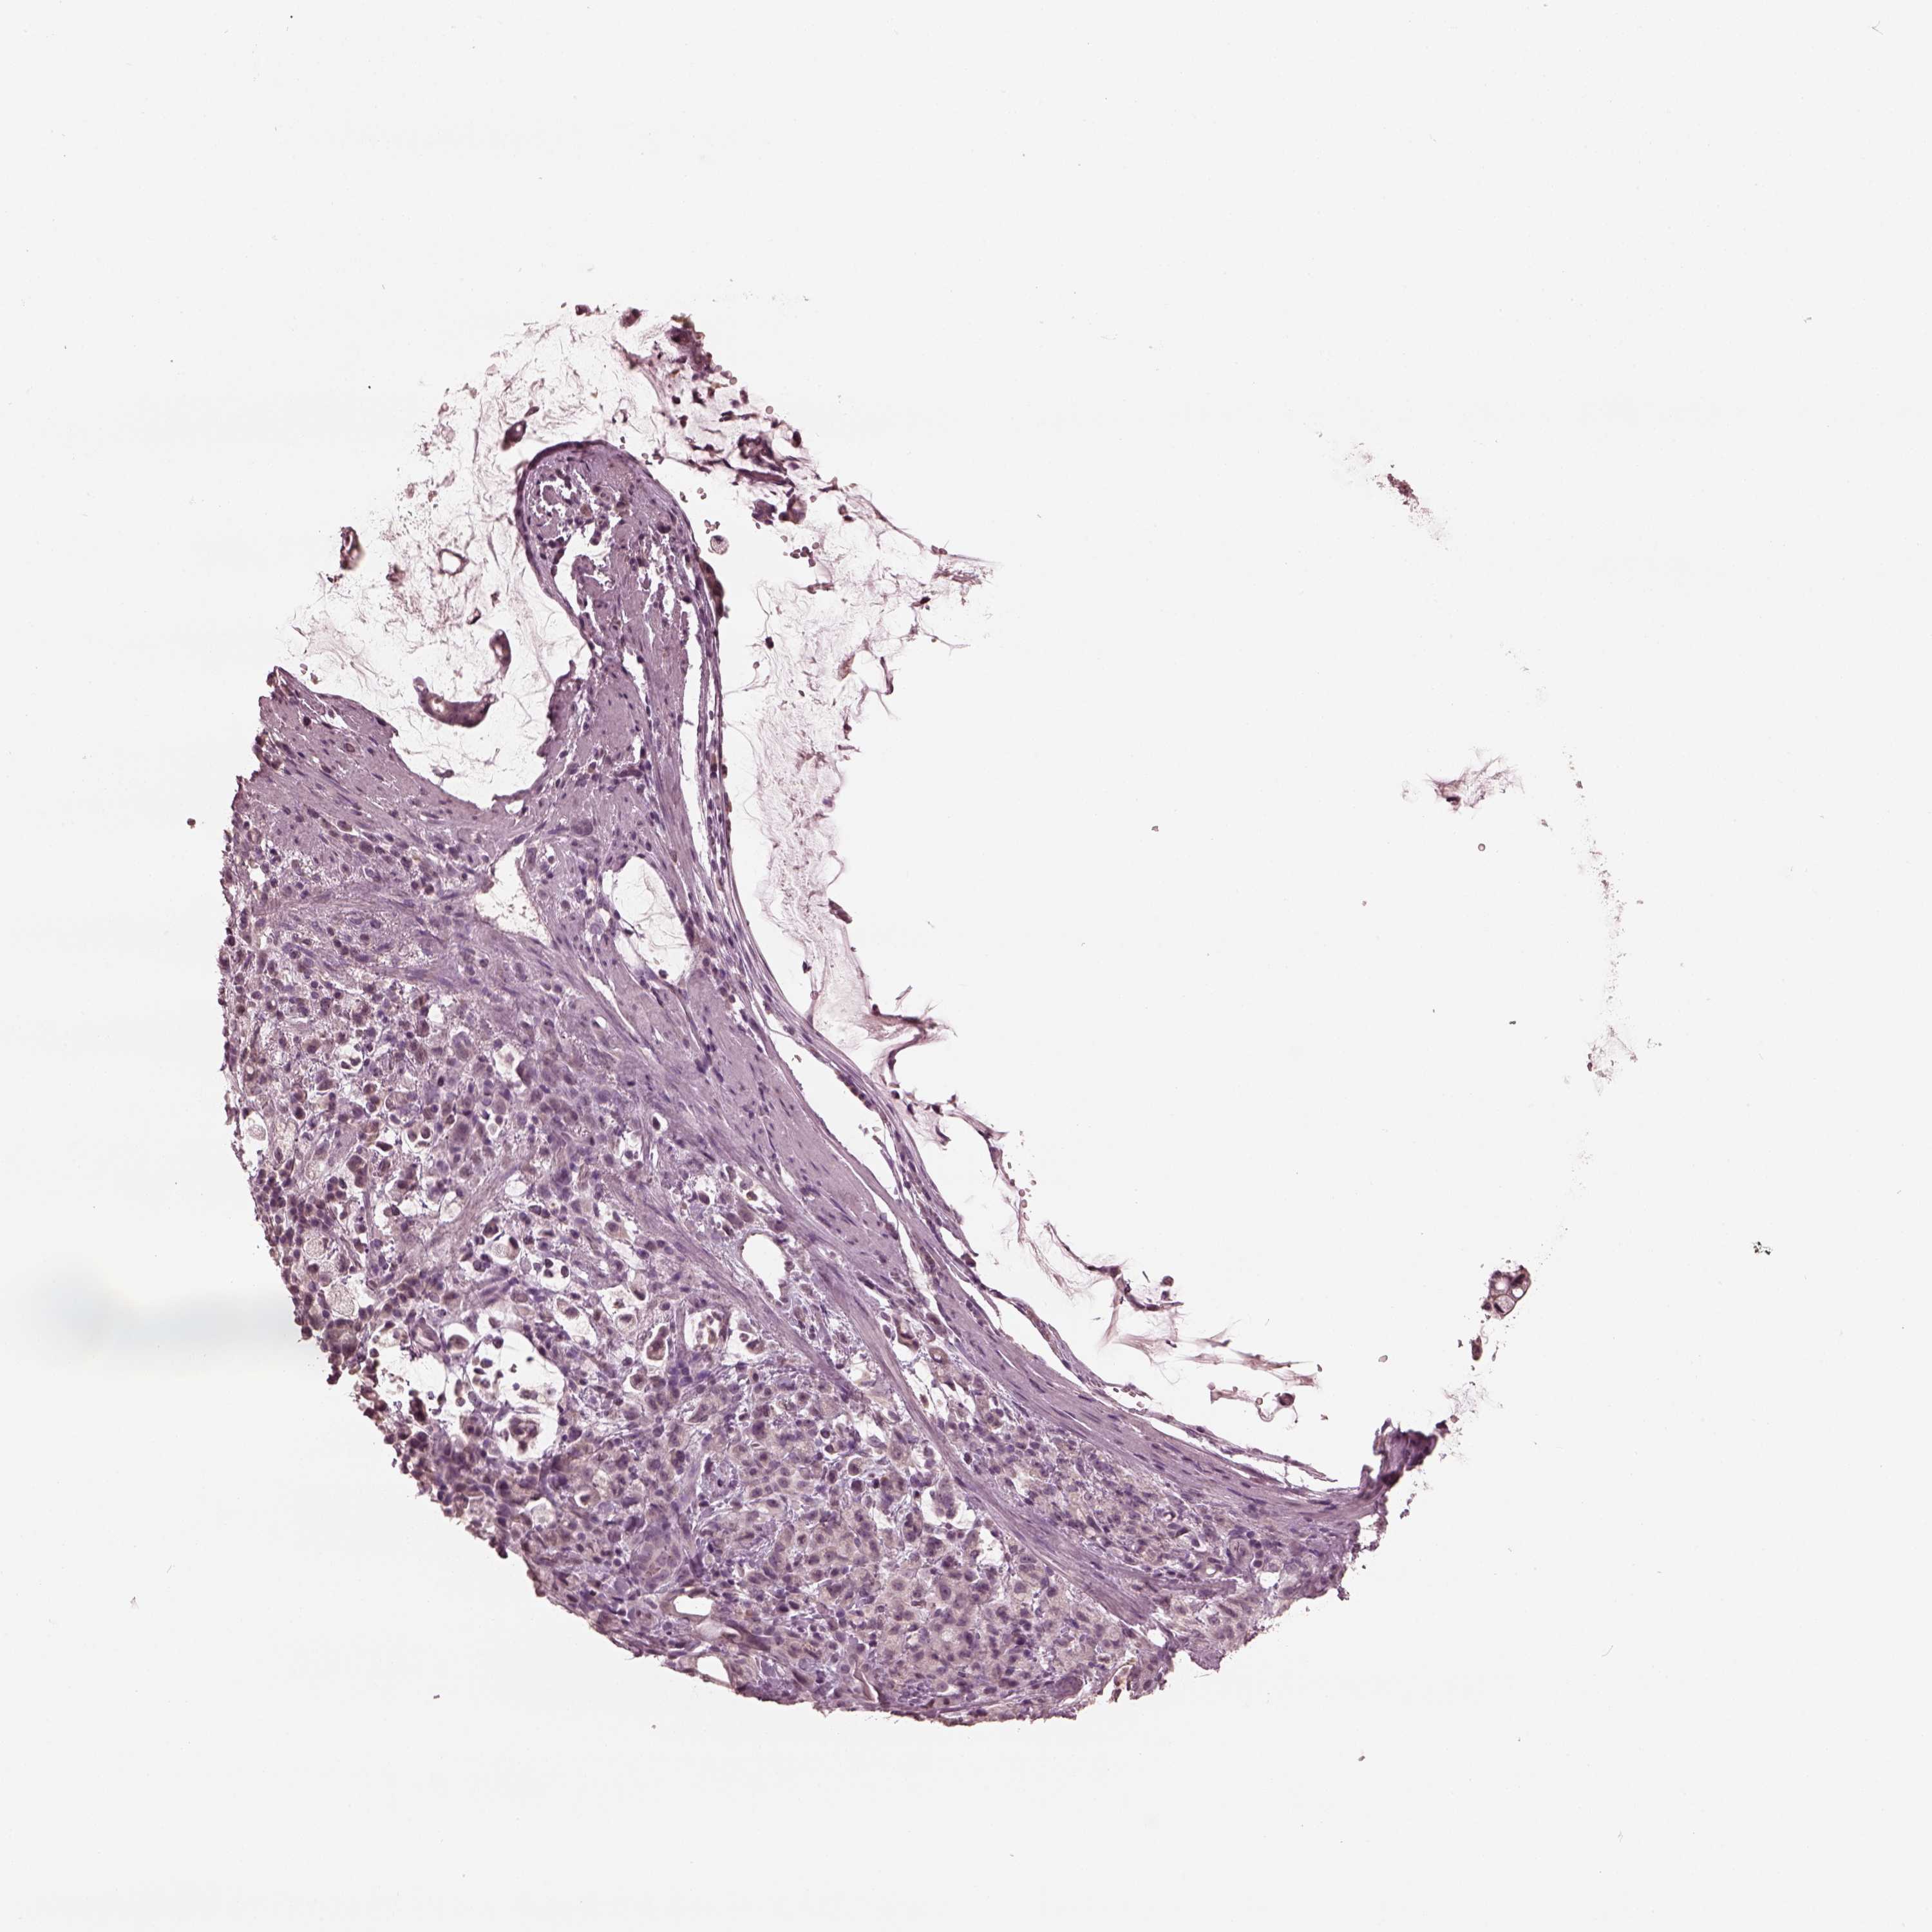

STOMACH CANCER - Protein expressioni

A mouse-over function shows sample information and annotation data. Click on an image to view it in a full screen mode. Samples can be filtered based on level of antibody staining by selecting one or several of the following categories: high, medium, low and not detected. The assay and annotation is described here.

Antibody stainingi

Antibody staining in the annotated cell types in the current human tissue is reported as not detected, low, medium, or high, based on conventional immunohistochemistry profiling in selected tissues. This score is based on the combination of the staining intensity and fraction of stained cells.

Each image is clickable and will lead to virtual microscopy that enables deeper exploration of all samples and also displays staining intensity scores, fraction scores and subcellular localization as well as patient and tissue information for each sample.

Antibody HPA059347

Staining

High

Medium

Low

Not detected

Intensity

Strong

Moderate

Weak

Negative

Quantity

>75%

75%-25%

<25%

None

Location

Nuclear

Cytoplasmic/membranous

Cytoplasmic/membranous,nuclear

Adenocarcinoma, NOS